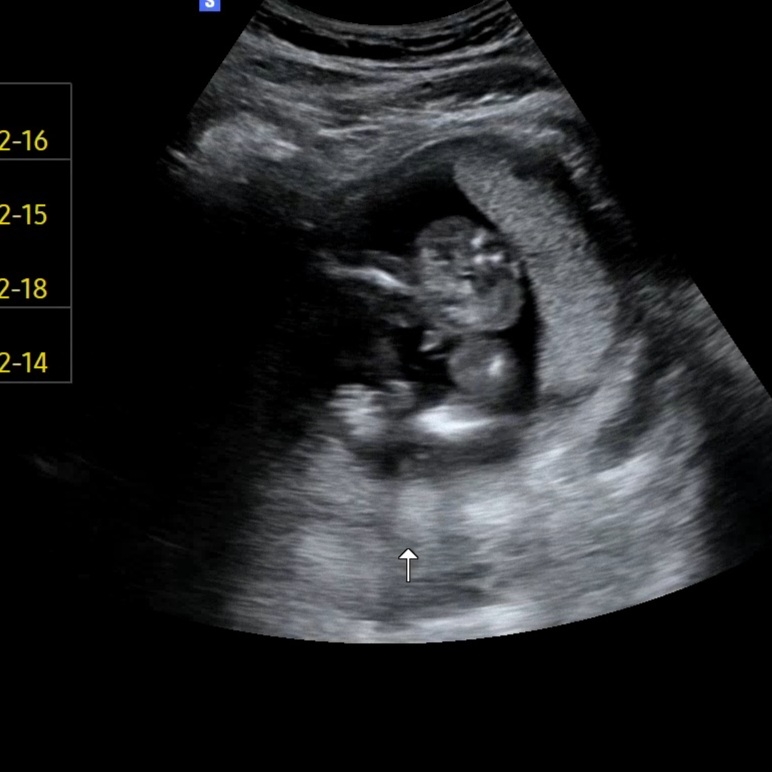

저것은.. 아들일까요...?

16주 5일인데..ㅋㅋㅋㅋㅋㅋㅋㅋ 아들일까요..? 갈라짐이 있어도 저건 아들일까요...? 한번씩만 봐주세요..킼키키킼....

아들같아요!

골반 사이인데 아들이겠..져..?